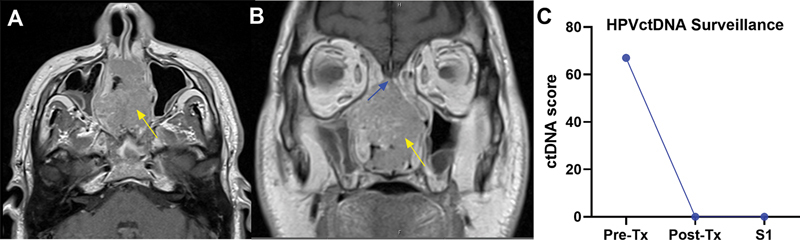

Case reports: We report two cases demonstrating the utility of ctDNA in HPV-mediated sinonasal malignancies. Case 1: 60-year-old male who presented with a large nasal cavity cancer. Pretreatment ctDNA testing yielded a positive tumor tissue modified viral (TTMV)-HPV DNA Score of 67, reflective of the normalized tumor tissue modified viral-HPV DNA fragments/mL of plasma, and pathology confirmed HPV+ SNSCC. Posttreatment surveillance with HPV ctDNA and endoscopy has shown no evidence of disease. Case 2 involves a 64-year-old male with HPV+ neuroendocrine carcinoma who developed recurrence. ctDNA testing, previously negative following initial treatment, scored 35 at recurrence, prompting salvage surgery and adjuvant chemoradiation.